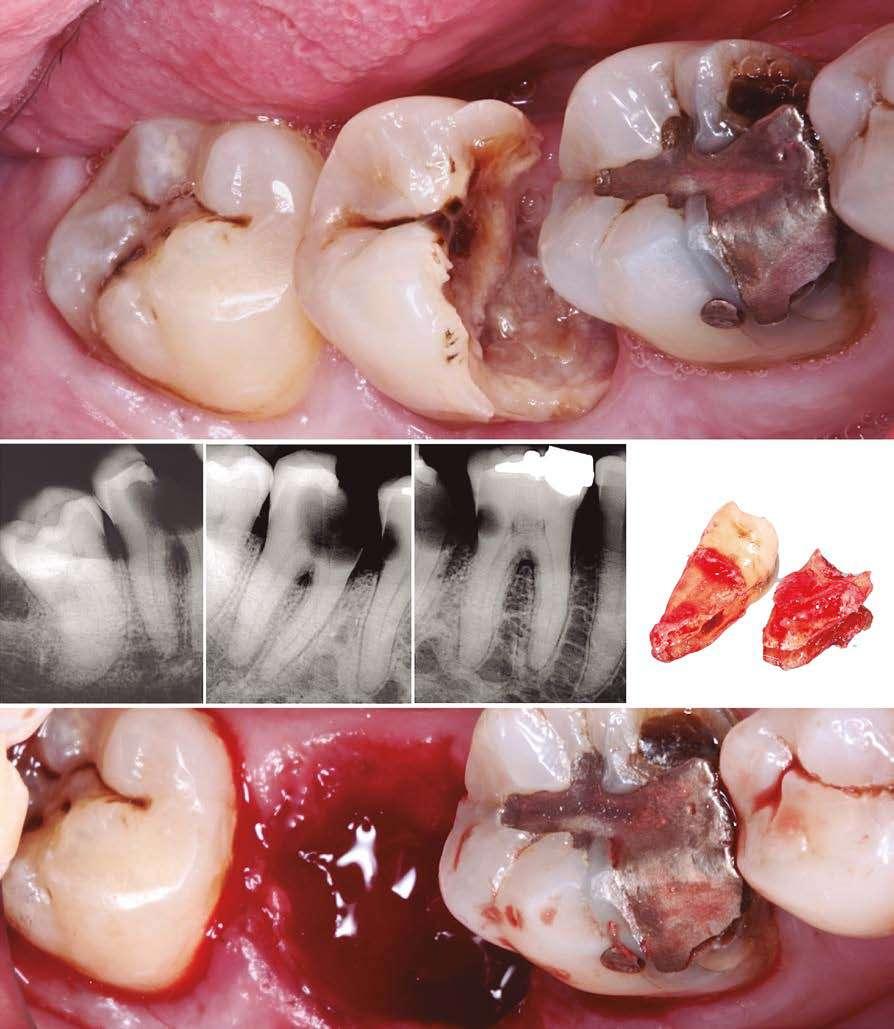

PROTOCOLOS DE AUTOTRASPLANTE POSEXTRACCIÓN: ¿INMEDIATOS

O DIFERIDOS?

El autotrasplante dental se está convirtiendo en una opción predecible en la odontología restauradora contemporánea. Sin embargo, las condiciones del alvéolo receptor pueden variar notablemente según el momento de la pérdida del diente y el tipo de diente a extraer. El objetivo de este artículo es presentar protocolos de autotrasplante posextracción basados en la planificación digital y describir los criterios de selección para cada una de las diversas opciones.

Introducción

El autotrasplante consiste en la extracción de un diente de su posición original y su posterior colocación en una posición distinta de la arcada dentaria del mismo paciente (Natiella y cols. 1970). Para realizar este procedimiento quirúrgico se pueden utilizar dientes donantes que estén erupcionados, dientes impactados o parcialmente impactados, independientemente del grado de formación radicular (Plotino y cols. 2020). Además, el autotrasplante puede realizarse tanto en situaciones posextracción inmediata como en alvéolos que hayan sido previamente preparados de forma quirúrgica (Abella y cols. 2021a).